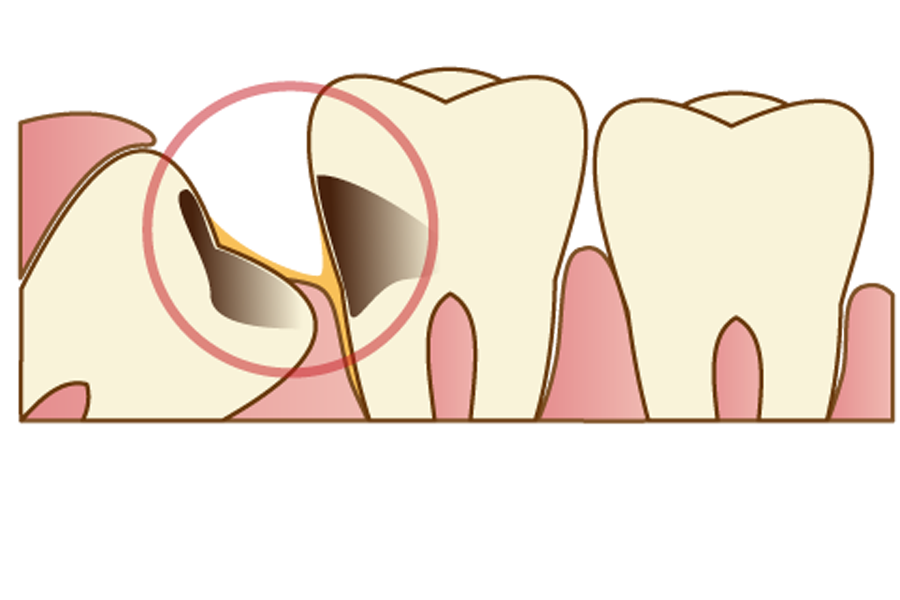

親知らずが斜めや横向きに生えている場合

親知らずがまっすぐ生えておらず、斜めや横向きになっている場合、汚れが溜まりやすく虫歯や歯周病のリスクが高い状態になっていると言えます。

身体が健康で免疫力が高く、しっかりと口腔ケアができているときは症状が抑えられますが、体の免疫力が落ちたり、妊娠出産などで歯周病リスクが高まる時期にトラブルを起こしてしまうケースが多々あります。

また、親知らずが隣の歯を押すことで、歯並びが悪くなったり歯が弱くなったりしてしまう可能性もありますので、将来的にトラブルが予想される親知らずの場合は早めに抜いておくことをおススメします。

親知らず自体が、虫歯や歯周病になっている場合

親知らずがむし歯や歯周病になっている場合、まわりの健康な歯にも影響が及ぼんでしまう可能性がありますので、抜歯した方が良いでしょう。